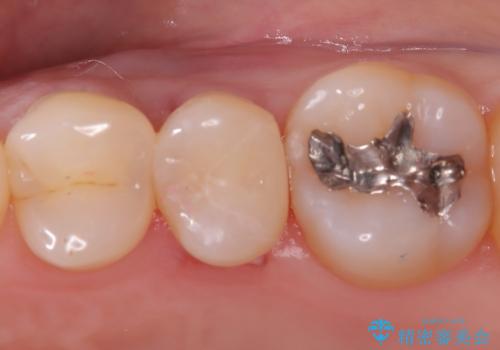

- 初診時にお口の中をチェックしたところ虫歯があり、大きさから部分的な詰め物のお話をしました。材料の特性を説明し、再び虫歯になりにくいセラミックインレーを選択されました。

セラミックインレー接着時にはラバーダム防湿を行いました。